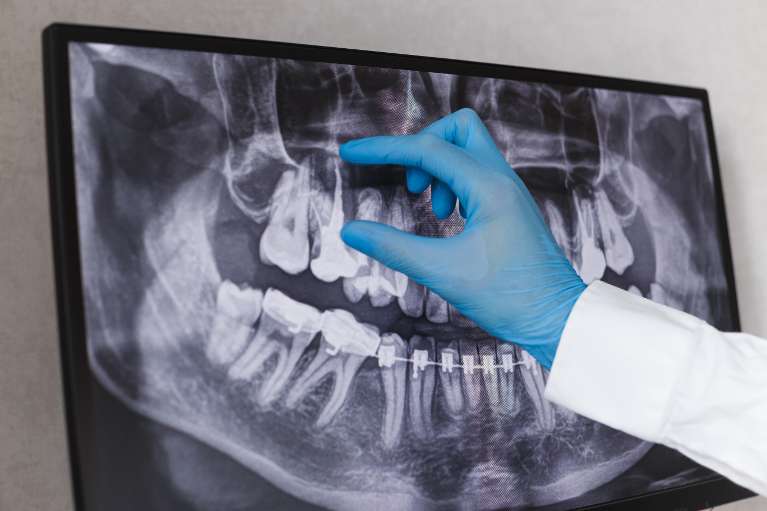

OPG X-Rays

An orthopantomogram (OPG) is a panoramic scanning dental x-ray that captures a two-dimensional view of the upper and lower jaw, including teeth, jaws and temporomandibular joints. Unlike periapical or bite-wing x-rays, an OPG x-ray captures a wide-view of the mouth in a single image. The OPG increases our vision of the upper and lower jaws, allowing us to prescribe treatment accurately.

An OPG x-ray can reveal dental concerns, such as:

- Cysts in the jaw bones

- Jaw tumours

- Oral cancer

- Advanced periodontal disease

- Impacted teeth and wisdom teeth

- Jaw disorders

- Sinusitis